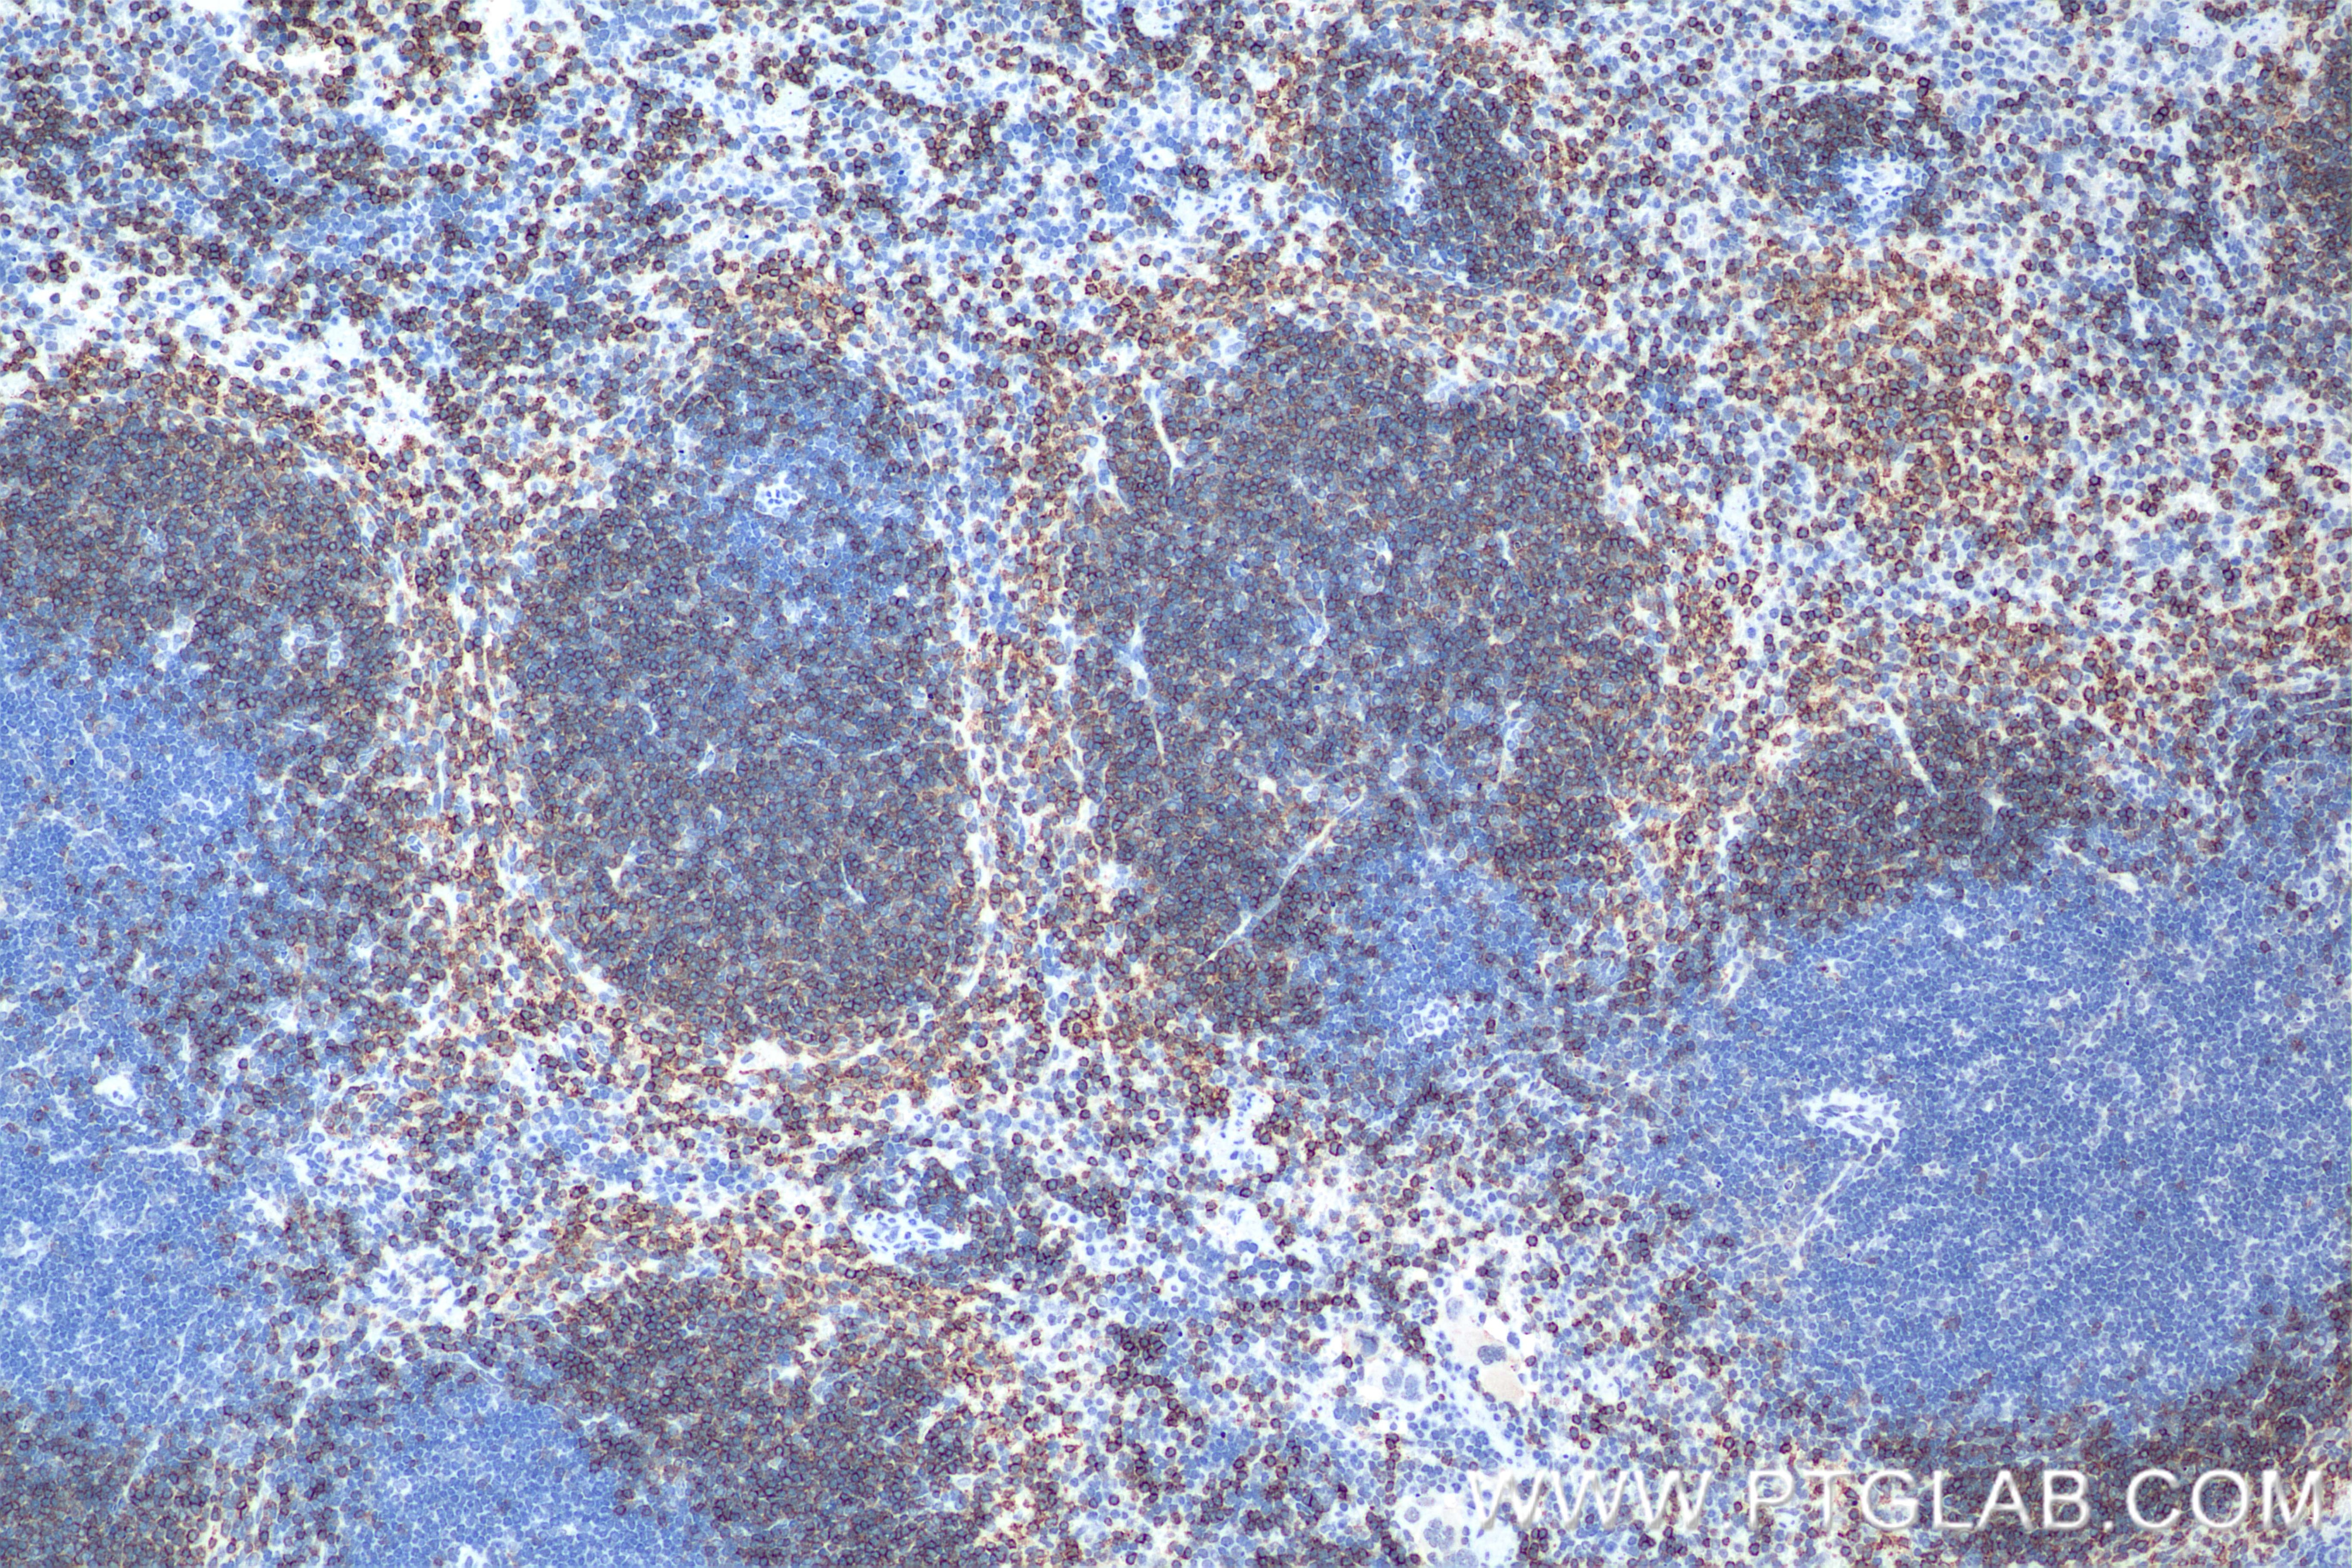

| Positive IHC detected in | mouse spleen tissue Note: suggested antigen retrieval with TE buffer pH 9.0; (*) Alternatively, antigen retrieval may be performed with citrate buffer pH 6.0 |

| Immunohistochemistry (IHC) | IHC : 1:5000-1:20000 |